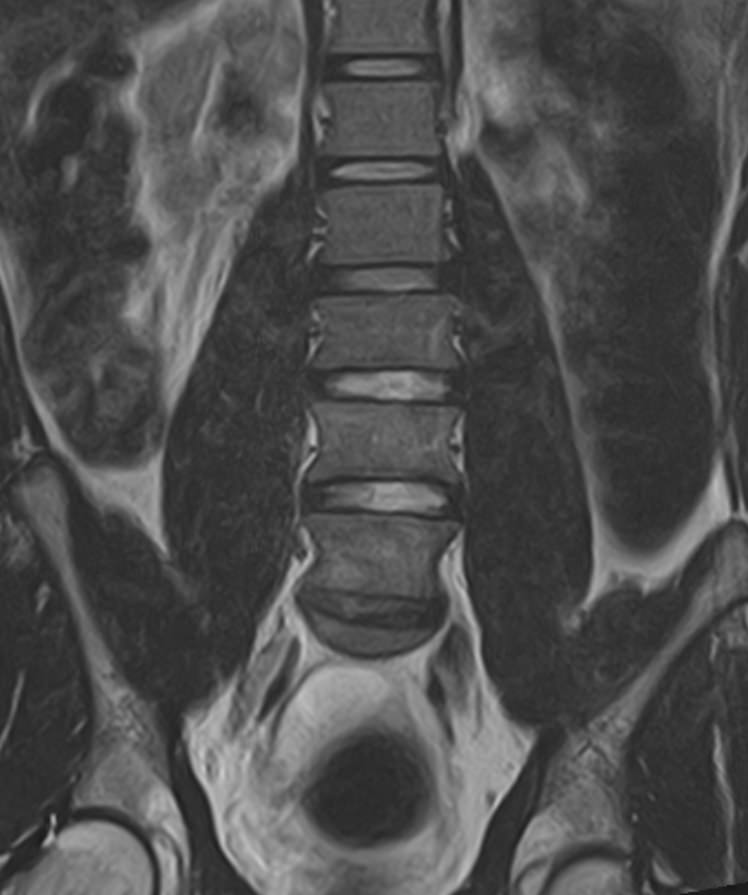

Наиболее точным и эффективным способом диагностики причин появления болей в нижней части спины является МРТ. С помощью данного метода можно оценить состояние всех анатомических структур позвоночного столба на исследуемом уровне, диагностировать поражение позвоночника на начальной стадии, когда другие методы не дают результатов. Такой патологией, в частности, является сакроилеит (воспаление крестцово-подвздошного сочленения), который часто становится причиной анкилоза (сращения) или нестабильности (патологической подвижности) сустава. Выявление сакроилеита на ранней стадии значительно улучшает прогноз в плане лечения и профилактики осложнений.

В клинике «Доступная медицина» диагностика патологии нижней части спины осуществляется на высокотехнологичном оборудовании – новейшем высокопольном томографе TOSHIBA VANTAGE TITAN 1,5 Тесла, который обеспечивает высочайшее качество изображений, точность и достоверность полученных данных. Магнитно-резонансная томография осуществляется без применения ионизирующего излучения, поэтому является безопасным методом обследования и может применяться неоднократно по мере необходимости.

Что можно диагностировать при проведении МРТ пояснично-крестцового отдела позвоночника + МРТ крестцово-подвздошных сочленений

При проведении данного комплексного обследования можно выявить:

• дегенеративно-дистрофические заболевания позвоночника: спондилез, спондилоартроз, остеохондроз;

• стеноз (сужение) позвоночного канала;

• грыжи межпозвонковых дисков (протрузии, экструзии);

• переломы позвонков, их смещение;

• спондилиты, гнойные артриты, сакроилеит, абсцессы околопозвоночных тканей и другие воспалительные заболевания, туберкулез;

• опухоли позвоночника и окружающих тканей;

• патологические изгибы позвоночника, сколиоз, усиленный или выпрямленный лордоз как нарушение статической функции позвоночника;

• аномалии строении позвоночника.